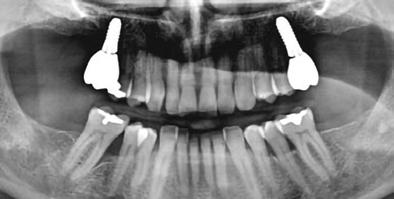

A pótlásra szoruló fogat, vagy fogakat minden esetben legalább egy évvel a fogpótlást megelőzően eltávolítottuk. Ezen esetek egyikében sem végeztünk alveolus vagy állcsontgerinc prezervációt az eltávolítás során, illetve minden páciens jó szájhigiéniával rendelkezett. Egy kivételével minden páciensnél radiológiai analízist végeztünk CBCT-vel,

amelyet

digitális implantátumtervezés követett (SICAT és Sidexis, mindkettő Dentsply Sirona; 1. ábra).

Mind a hat implantátum esetén kétlépcsős műtétet végeztünk. Minden sebészeti eljárást bódítás, illetve preoperatív szisztémás antibiotikus terápia nélkül végeztünk. A négy eset közül kettőnél leukocitában és vérlemezkében gazdag fibrint (L-PRF) alkalmaztunk a beavatkozás során (IntraSpin, BioHorizons; 2. táblázat). Minden esetben a pontos CERALOG menetvágási (maximum 15 ford./perc) és fúrási (maximális fúrási fordulatszám: 550–800 ford./perc) protokollt követtük. Az összes implantátumot manuálisan helyeztük be 35 Ncm maximális nyomatékkal. Az implantátumokba PEEK zárócsavar került (2. ábra). A lágyszövetet atraumatikus, felszívódó varrattal, szorosan zártuk/összevarrtuk. A műtétek után szövődmények nem jelentkeztek. A pácienseket arra kértük, hogy a műtét utáni héten naponta kétszer öblögessenek klórhexidinnel (PERIO-AID, 0,05%, DENTAID). Az alsó állcsontnál három hónapos, a felső állcsontnál öt hónapos gyógyulási időt vettünk figyelembe. Három hónap (1. eset) és öt hónap (2., 3. és 4. eset) elteltével a műtétek második stádiumát helyi érzéstelenítés mellett végeztük. A gyógyu-

lási csavarokat (PEEK titáncsavarral) maximum 15 Ncm-rel húztuk meg (3–6. ábra). Az összes implantátum kiváló stabilitást mutatott (a mérésekhez Periotestet használtunk, a Medizintechnik Gulden jóvoltából), és teljesen osszeointegrálódott. Ezt a radiológiai vizsgálatok is megerősítették.

2a 3a 4a 2b 3b 4b 2c 2d Pozíció Implantátum átmérő Implantátum hossz L-PRF Behelyezési nyomaték Eset 1 #35 4 mm 12 mm Nem 35 Ncm Eset 2 #25 4 mm 12 mm Nem 30 Ncm #26 4 mm 8 mm Nem 25 Ncm Eset 3 #16 4 mm 8 mm Igen 25 Ncm #26 4 mm 10 mm Igen 30 Ncm Eset 4 #26 4 mm 10 mm Igen 30 Ncm

2. a–d ábra: PEEK zárócsavarok az implantátumokba helyezve, 1. eset (a). 2. eset (b). 3. eset (c), 4. eset (d). 3. a–b ábra: Röntgenfelvételek három hónap után (a) és a gyógyulási csavarok behelyezve (b, 1. eset). 4. a–b ábra: Röntgenfelvételek öt hónappal később (a) és a gyógyulási csavarok behelyezve (b, 2. eset). 2. táblázat: Az implantátum tulajdonságai.